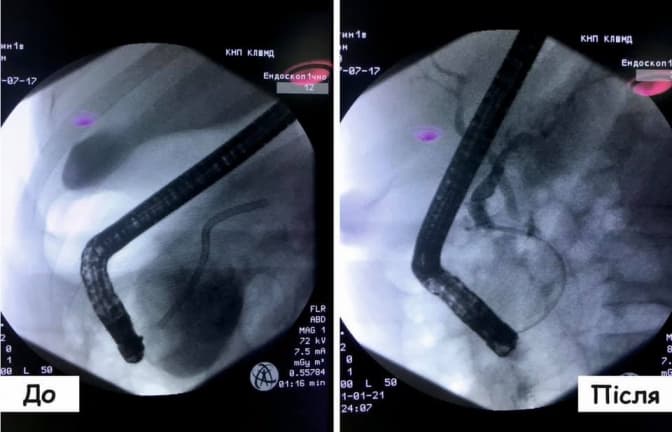

Маючи розмір 64х59х67 мм, ця псевдокиста здавлювала 12-типалу кишку, викликала біль і заважала проходженню їжі. Тож для допомоги хворому фахівці Блоку панкреато-біліарної рентген інтервенційної ендоскопії застосували один із сучасних методів лікування – ендоскопічну ретроградну холангіопанкреатографію.

«Це – ендоскопічне стентування протоки підшлункової залози через заведення ендоскопа в порожнину 12-типалої кишки. Таким чином пацієнтові спорожнили кисту через протоку підшлункової залози, поставили стент та взяли на посів її вміст», – пояснюють у медазкладі.

«Зазвичай, така складна операція проводилася «відкритим» оперативним втручанням, та вона могла мати важкі наслідки для пацієнта та довгим реабілітаційним періодом – до трьох місяців. Та завдяки правильно підібраний методиці лікування через два місяці чоловіка чекає лише видалення стента, а також контрольний огляд», – додають там.